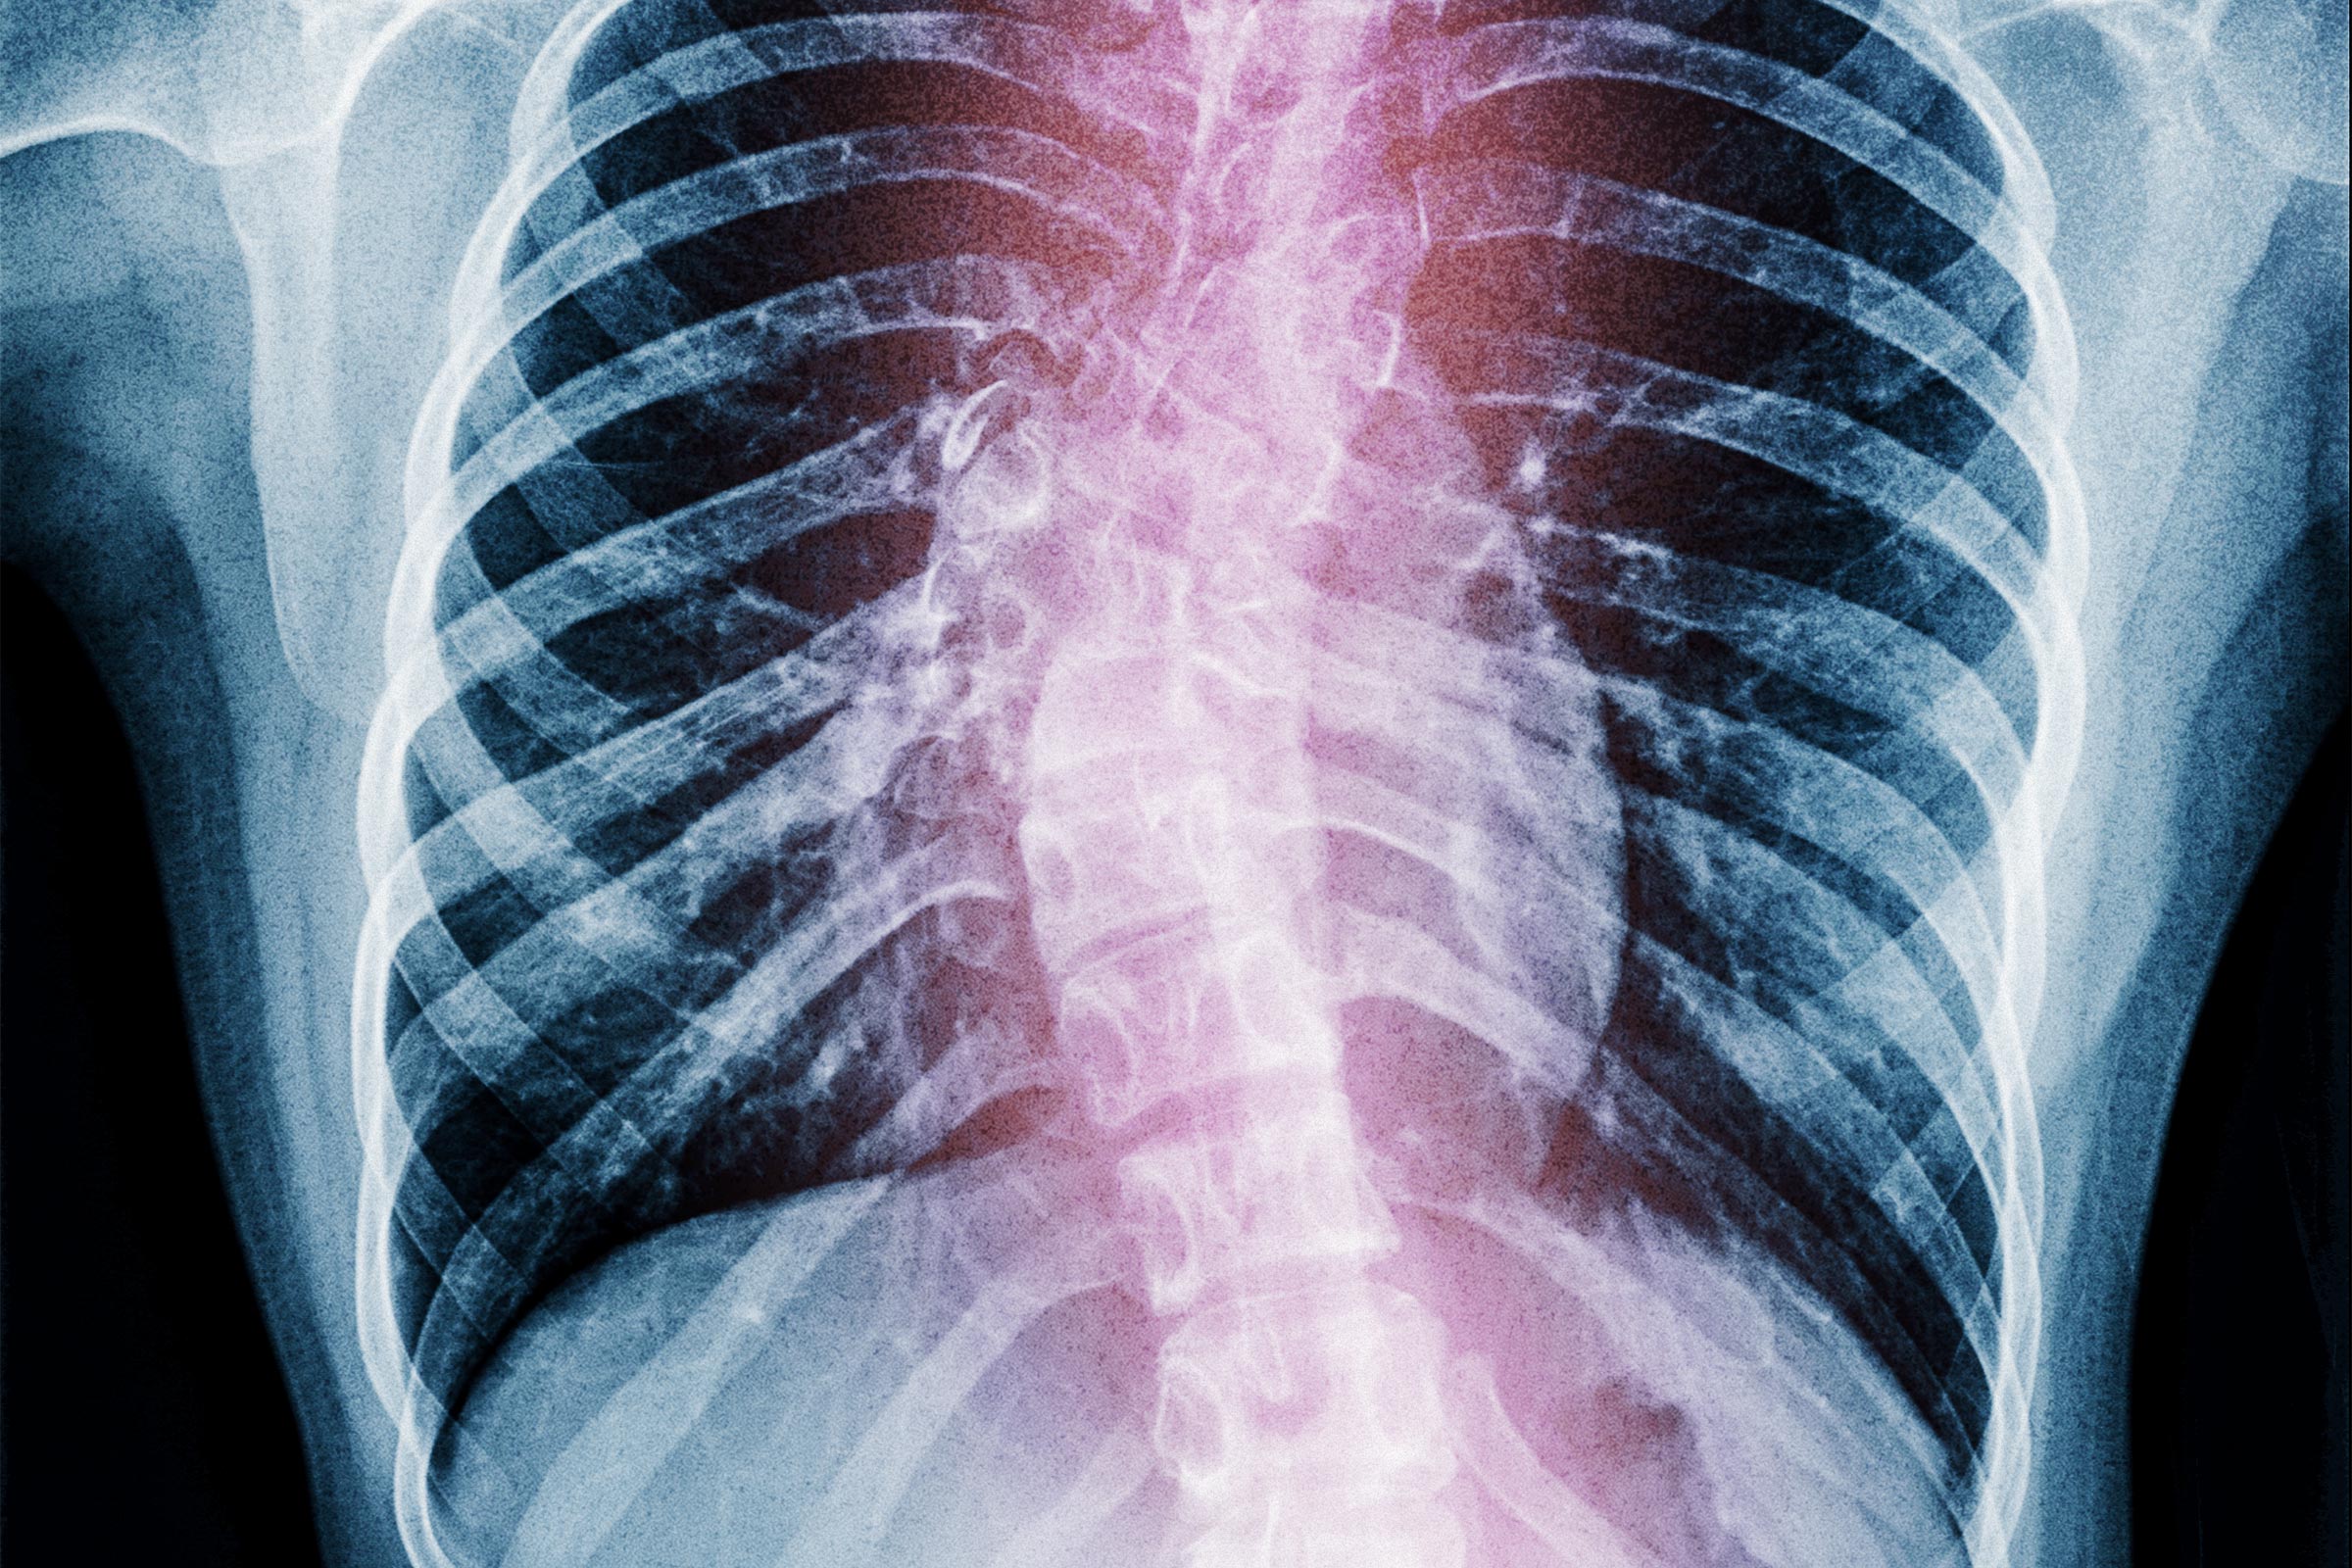

A healthy spine is naturally straight, allowing free movement and an aligned posture. However, when scoliosis exceeds a critical angle, it can trigger respiratory distress, arrhythmias, lower limb paralysis, or severe pain.

“Severe scoliosis directly affects the structure of the thorax [the upper area of the trunk between the neck and the abdomen],“ Xie said. ”When the spinal curvature exceeds 40 degrees, the chest cavity is compressed, restricting lung expansion—breathing can feel as if a tight belt is cinched around the chest.

“The thoracic spine acts as natural armor protecting the heart and lungs—once severe scoliosis occurs, it directly threatens life.”

Research has found that patients with thoracic scoliosis exceeding 80 degrees are highly likely to experience respiratory distress, with severe cases potentially leading to cardiopulmonary failure.